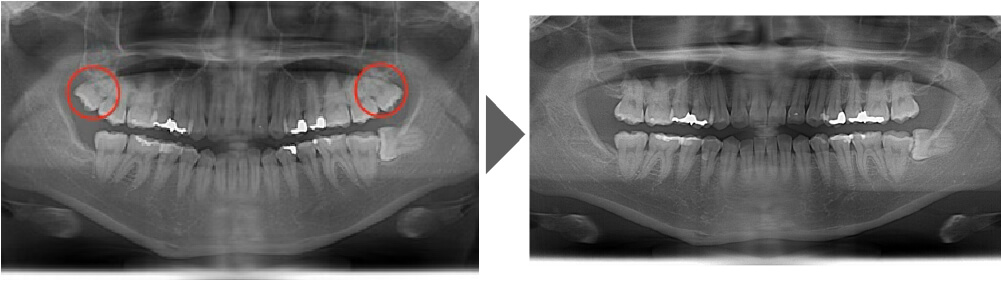

抜歯症例②

しっかり生えており、非常に磨きづらく虫歯のリスクの高い歯です。 上を2本とも抜歯しました。

【抜歯所要予約時間】

各15分

(麻酔の時間があるので処置自体はもっと短いです)